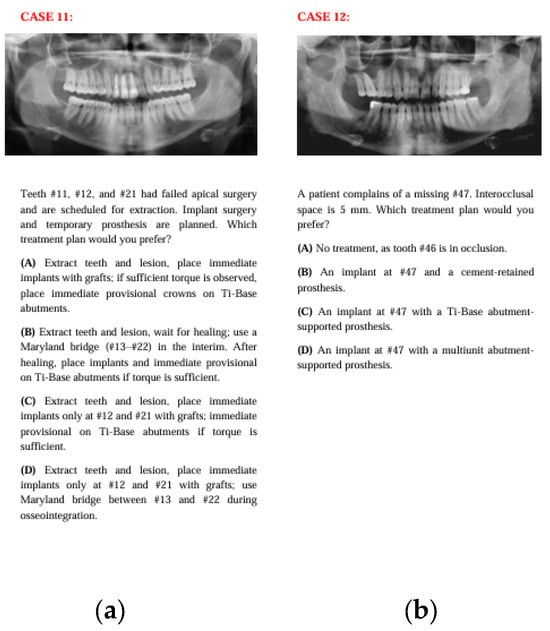

Figure 6. The panoramic radiographs, descriptions, and four treatment options of Case 11 (a) and Case 12 (b).